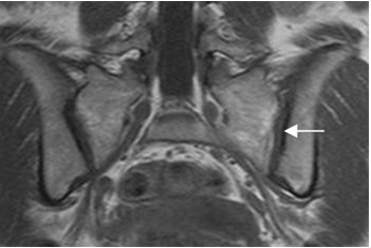

Normalmente se identifica el cartílago articular, como una estructura delgada y con señal de intensidad (SI) intermedia en T1 e hipointensa en T2. (2). (Fig 4 y 5).

Fig 4. Cartílago normal.

RM vista coronal en T1. Cartílago con SI intermedia.